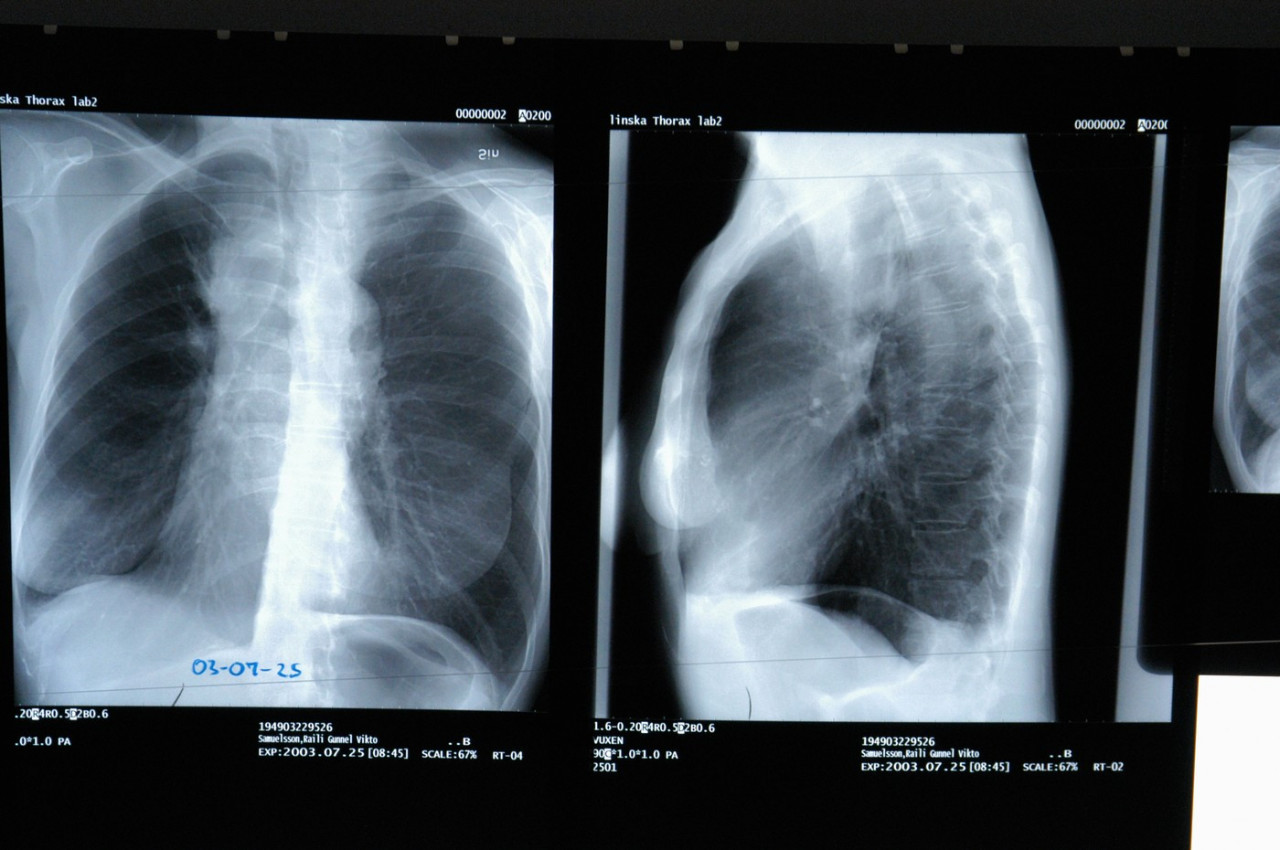

Шта је обострана упала плућа и који су симптоми?

Обострана пнеумонија је стање доста озбиљније од упале плућа и док се обострана пнеумонија не разликује превише од пнеумоније која погађа једно плућно крило, када инфекција или упала утичу на већу површину плућа, вероватно ће бити озбиљније стање.

Симптоми обостране пнеумоније

Не постоји стварна разлика у типу симптома двоструке, обостране упале плућа у односу на упалу плућа која погађа једно плућно крило. Код појединачне пнеумоније, осећа се бол у грудима, али само на једној страни. Код обостране, јавља се са обе стране. Али, будући да обострана пнеумонија погађа оба плућна крила, ово стање је теже.